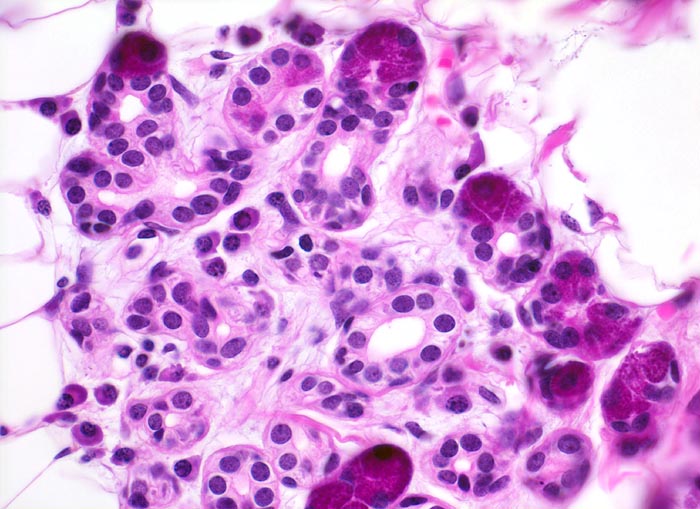

Adenoidzystische Karzinome zeigen drei Wachstumsmuster (in abnehmender Reihenfolge): kribriform, tubulär und solide. Die Hohlräume in den kribriformen Arealen entsprechen keinen echten Drüsenlumina, sondern sind Bestandteil des Tumorstromas. Sie enthalten PAS positives Sekret oder hyaline Substanzen. Die strangförmigen Tubuli begleitet von hyalinem Stroma. Typischerweise (allerdings nicht im vorliegenden Präparat) kann eine Perineuralscheideninvasion nachgewiesen werden. Kleine Tumoren können scharf begrenzt sein, grössere Tumoren wachsen infiltrativ.

• Mikrozystische Hohlräume in den kribriformen Tumorarealen enthalten eosinophiles hyalines Material.

• Tubuli mit zentralem Lumen werden ausgekleidet von einer inneren helleren Epithelschicht und einer äusseren dunkleren Myoepithelschicht.

• Basaloide kleine Tumorzellen mit wenig Zytoplasma.